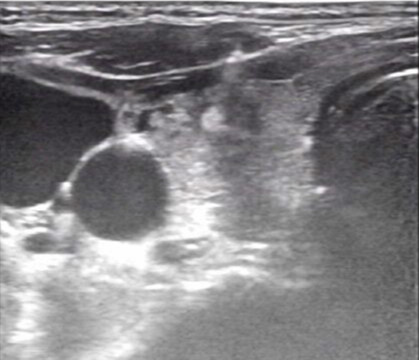

超声引导下的甲状腺结节细针穿刺活检术(US-FNAB)是指在高频超声引导下,应用无菌穿刺针(通常22-25G的甲穿专用针)穿刺甲状腺结节可疑部位,抽取部分结节成分送细胞学病理检测的一种鉴别甲状腺良恶性的方法。甲状腺结节是临床上最常见的甲状腺病变。超声在甲状腺结节评估中具有很高的敏感性及特异性,然其仅能对甲状腺结节的实现初步评估,无法给予明确的定性诊断。目前超声引导下细针穿刺活检已成为甲状腺结节评估的金标准。一方面提供甲状腺结节的重要信息如回声情况、边界、形状,有无钙化、血流情况等。另外一方面赋予细针穿刺活检精确定位的优势,极大降低了假阴性穿刺及取样的不满意情况。

超声引导下细针穿刺活检应用于临床以来,由于其对可疑甲状腺结节特异筛选及对穿刺靶向定位作用,对绝大多数结节均能实现术前评估,从而减少良性结节患者的不必要手术;并能检出恶性结节患者,使其得以及时治疗,减轻了患者病痛,节约了医疗资源。具有安全可靠、创伤小、 并发症少、取材方便、无针道转移等优点,是目前国内外各大甲状腺结节指南所推荐的、用于鉴别甲状腺结节性质的首选诊断方法。